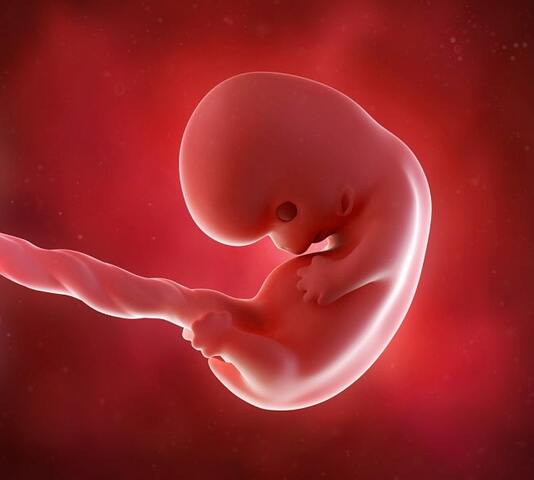

• Period: 15 to 63

Segunda etapa

El embrión constituye esta etapa. Comienza cuando se logra la implantación en el útero. Abarca desde la tercera semana a la novena

• Aparición del corazón

21

Aparición del corazón

Al final de la tercera semana aparece un pequeño corazón que se conecta a la venas

• Desarrollo de órganos y bultos

28

Desarrollo de órganos y bultos

Durante la cuarta semana se comienzan a desarrollar los brazos, la cabeza y los órganos sensoriales